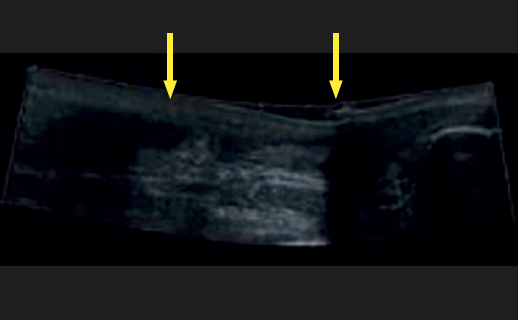

La resonancia magnética (RM) y la ecografía se han propuesto como técnicas diagnósticas complementarias y pueden ser útiles cuando la inflamación de las partes blandas dificulta la exploración física; la literatura considera la especificidad de la RM superior a la de la ecografía(9) (Figuras 5 y 6).